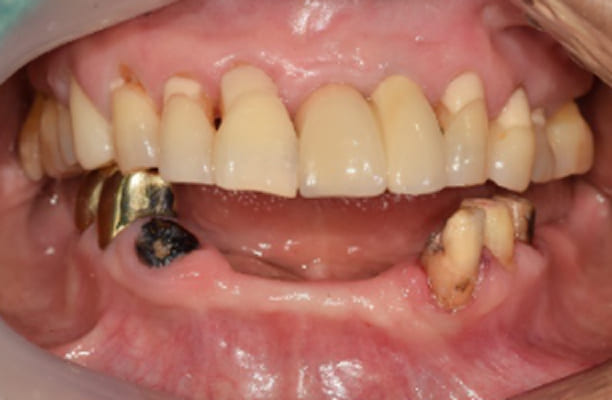

-

术前 -

术后